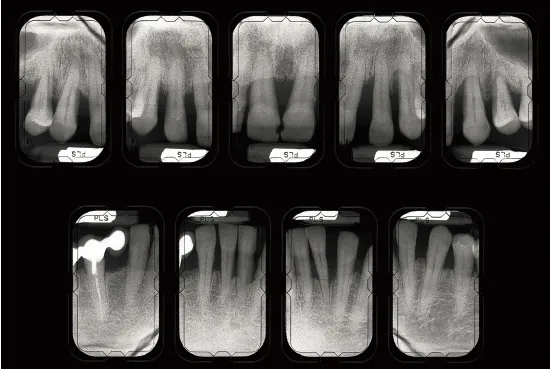

Fig 1-1a Aggressive periodontitis in a 40-year-old woman who is subject to stress and smokes one pack of cigarettes a day. The patient experienced an emotional shock 5 years earlier. A conventional treatment plan was initiated and included periodontal surgery throughout all quadrants. Professional maintenance (scaling and root planing) was carried out every 3 months, and the patient responded well.

Fig 1-1b Four years after treatment and maintenance therapy. Periodontal status has deteriorated in all areas. Observe the new attachment losses, dental migrations, and larger diastemata. It is clear that periodontal disease is not controlled. This patientās disease was refractory to conventional treatment. Specific risk factors in this patient were underestimated.